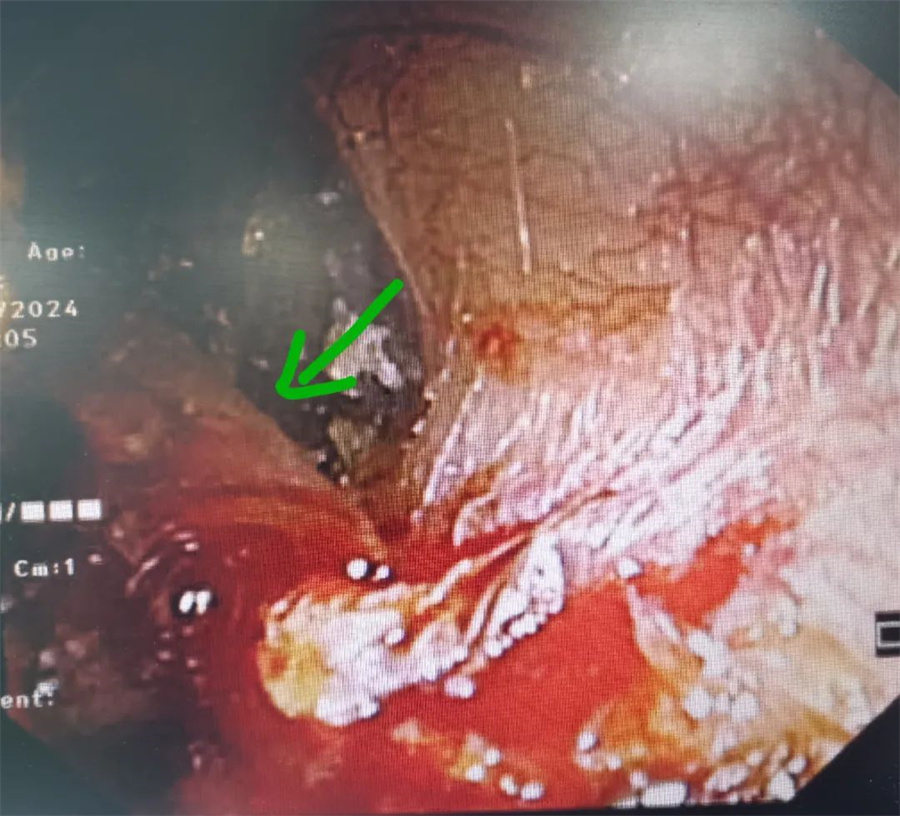

耳鼻喉科医生接诊后,经检查发现,掏耳勺的前端已经接触到了鼓膜,耳道后壁皮肤受损。于是,当即为孩子做了全麻下耳道异物取出术,仅用半分钟,就将残留的掏耳勺取出。

取出后再次检查发现,孩子左耳鼓膜和耳道交界处有血痂,幸运的是,没有出现穿孔,第二天就回家静养。